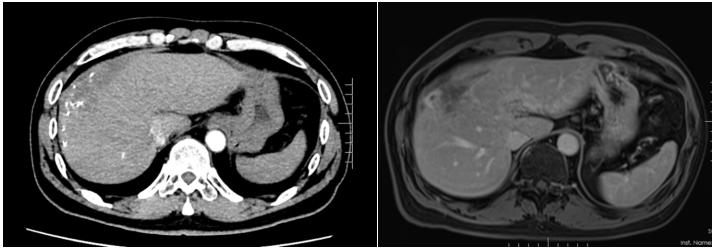

患者入院时诉说了自己与晚期肝癌对抗的痛苦与不易,同时也表明了与病魔抗争到底的决心。入院后,龙奎副主任医师立即为患者完善了CT、MRI+MRCP,ICG等检查,经过术前多学科MDT讨论后,认为患者肝癌转化效果满意,可以手术治疗。

手术中,由于患者有门静脉海绵样变特别容易出血,转化治疗后肝内管道走行变异,手术过程尤其艰难。龙奎副主任医师、董文志副主任医师、孙翊程医师与樱花动漫 优秀的麻醉团队、手术室护士团队通力合作,利用医院先进的荧光腹腔镜导航辅助,精准地完成了腹腔镜下肝IVb段+V段+胆囊切除术,历时5个小时,出血量200ml。